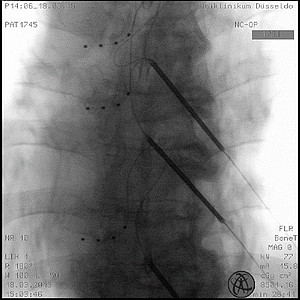

Spinal Cord Stimulation (SCS)

Dieses Verfahren ist die „klassische“ Anwendung der Neuromodulation. Mit dieser gezielten Therapie lassen sich sehr viele Schmerzsyndrome gut behandeln. Es werden hierbei operativ ein bis zwei Elektroden in den Rückenmarkskanal gelegt. Die Anlage kann über die gesamte Länge der Wirbelsäule erfolgen, von der Hals- bis zur Lendenwirbelsäule. Die Stimulation kann über zwei Arten erfolgen: zum einen als angenehmes Kribbeln im betroffenen Areal oder als sogenannte „stumme“ Stimulation, wobei der Schmerz gelindert wird, die Stimulation aber vom Patienten nicht wahrgenommen wird.